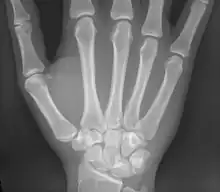

Les métacarpiens (ou os métacarpiens ou os du métacarpe) sont les os formant le métacarpe squelette de la paume de la main. Ils sont articulés dans leur partie supérieure[1] avec les os de la rangée distale du carpe et se prolonge au niveau de sa partie inférieure[1] par les phalanges proximales. Ces os sont unis par les muscles interosseux.

Les métacarpiens sont cinq petits os longs numérotés de 1 à 5, de dehors en dedans en position anatomique : 1 correspond au pouce et 5 à l'auriculaire. Chacun se compose d'une base proximale, d'un corps et d'une tête distale.

Les métacarpiens ont deux points d'ossification : un primaire dans la diaphyse pour la base et le corps et un secondaire dans la tête.

Pour le premier métacarpien, le point d'ossification secondaire est dans la base.